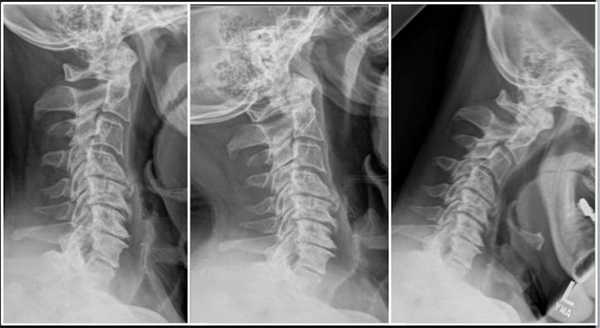

Подготовка к операции на шейном отделе позвоночника

Сначала врач направляет пациента на комплексное клиническое обследование, результаты которого становятся более понятны после визуализационной диагностики. Клиническое обследование — это беседа с пациентом и физический осмотр. Визуализационное обследование — это рентген в положении "лежа" и "стоя", то есть под нагрузкой. Еще одним немаловажным моментов диагностики является МРТ (магнитно-резонансная томография). Таким образом определяется состояние межпозвоночных дисков и нервов в области позвоночника. Помимо этого, проводится измерение плотности костей для установления их стабильности, а также исключения остеопорозных изменений.

Импланты шейного отдела позвоночника на рентгене.

Если клиника симптомов не поддается консервативной терапии или неинвазивные способы не могут быть задействованными ввиду сильно прогрессирующего стеноза, назначается операция. Вмешательство предполагает использование декомпрессионной ламинэктомии под общим наркозом. При комбинированной проблеме, например, вместе с грыжей, ее сочетают с микродискэктомией и спондилодезом. При спондилодезе осуществляют скрепление смежных позвонков металлическими фиксаторами (стержнями, пластинами, крючками и пр.), установку межтеловых имплантатов или вживление костного трансплантата с металлической гильзой.

Установка металлической конструкции.